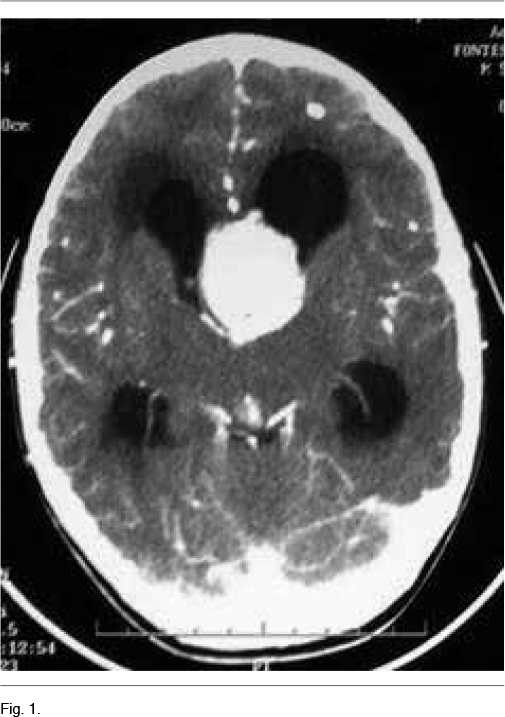

A los 5 años instala un síndrome de hipertensión endocraneana dado por cefaleas que progresan en el correr de tres meses, llegando los días previos a la consulta a despertarlo en la noche y a acompañarse de vómitos matinales que alivian las cefaleas. La tomografía computada de cráneo de urgencia informa un proceso expansivo de tercer ventrículo, que obstruye el agujero de Monro, determinando una hidrocefalia supratentorial de ambos ventrículos laterales, mayor a izquierda, con desviación de línea media a derecha de 12mm, edema transependimario e intensa captación de contraste (Figura 1). Con planteo de hidrocefalia secundaria a SEGA, se realiza en una primera instancia una derivación ventrículo-peritoneal de urgencia a nivel del ventrículo lateral derecho, para tratamiento de su hipertensión endocraneana descompensada. El procedimiento no presenta complicaciones, quedando el paciente asintomático luego del mismo. En el fondo de ojo post-derivación se observa edema de papila bilateral. La RM post-operatoria muestra el SEGA y la persistencia de una hidrocefalia a nivel del ventrículo lateral izquierdo. En una segunda instancia se realiza la cirugía del tumor lográndose una resección parcial del mismo, con un remanente tumoral de 14.3cm3 (Figura 2A) La anatomía patológica confirmó el diagnóstico de SEGA.